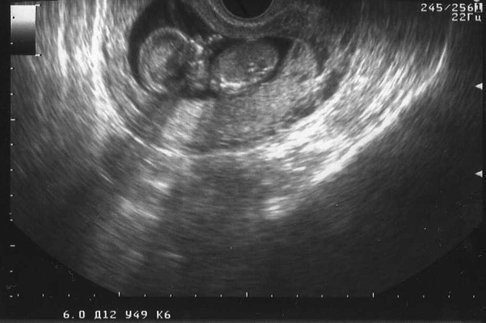

На двери отделения надпись: «Специализация — невынашивание беременности». Символично. Я приехала «на сохранение». Первое направление — на узи. Врач-узист, прервав переговоры с менеджером какого-то автосалона, пояснил: «На данном сроке мы ищем аномалии у плода, приводящие к угрозе выкидыша». Нашел:

— Один показатель высоковат, это по последним данным говорит о повышенном риске рождения ребенка с хромосомными аномалиями, такими, например, как…

— Да-да, я понимаю, спасибо, — пытаюсь выбежать поскорей. Хромосомные аномалии — это чаще всего синдром Дауна. Или Эдвардса. Что тут скажешь?

— Врач даст направление на генетическую экспертизу, — слышу в дверях как сквозь ватный матрас на голове.

Соседки ободряли: «Да ну его, это узи!». Вспоминали знакомых, у которых «в итоге оказалось все хорошо», одна женщина рассказала, что лежит повторно: малышу уже 20 недель, а ведь вначале узист диагностировал «замершую» беременность, предлагали прервать…

Ободряй — не ободряй, но надо знать, к чему готовиться. По запросу «синдром Дауна» интернет-поисковик сразу предложил сайты реабилитационных центров, медицинские статьи и… стихи мальчика с таким синдромом, опубликованные в «Фоме». Стихи! Не графоманию, не рифмоплетство… Вот тогда я поняла, что страх уходит, а вместо лукавого «может, само решится» водворяется жалость к моему малышу, который может быть таким чудесным — и таким недопонятым в мире.